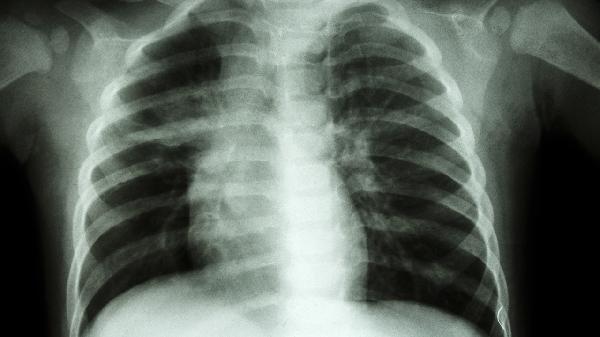

矽肺是一种不可逆的职业性肺病,药物治疗的主要目标是延缓疾病进展、控制症状、改善生活质量并预防并发症。患者务必在呼吸科或职业病科医生的全面评估和指导下进行规范治疗,切勿自行购药或更改治疗方案。除了药物治疗,生活管理也至关重要。患者应绝对脱离粉尘作业环境,这是防止病情加重的首要措施。注意预防呼吸道感染,天气变化时及时增减衣物,必要时可接种流感疫苗和肺炎疫苗。根据自身情况,在医生指导下进行适度的呼吸功能锻炼,如腹式呼吸、缩唇呼吸等。饮食上应保证营养均衡,摄入足够的优质蛋白和维生素,以增强机体抵抗力。戒烟并避免吸入二手烟,保持居住环境空气清新。定期复查胸部影像学和肺功能,以便医生及时调整治疗策略。保持乐观心态,积极配合治疗与康复。